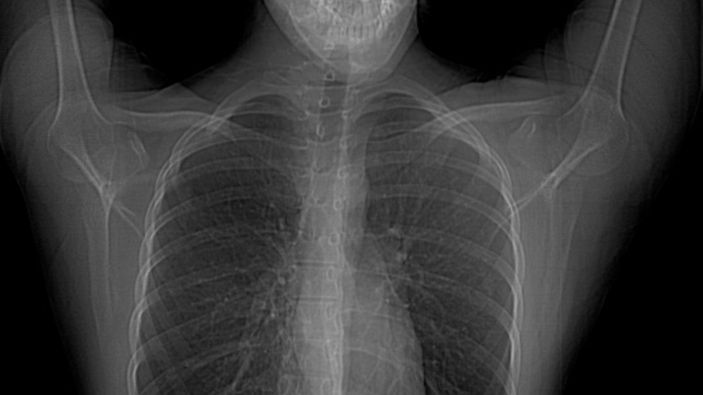

Hastanın vücut yapısı simetrik değildir. Yani vücudun bir yarısıyla diğer yarısı arasında görüntü ve yapı farklılıkları vardır. Özellikle göğüs bölgesinde bulunan yapılarda anormallikler bulunmaktadır. Kişide meme ve meme başı yokluğu da beraberinde görülebilmektedir.

Hastaların göğüs kası olmadığı için bakıldığında simetrik bir görünüm bulunmamaktadır. Estetik bir görüntü olmaması nedeniyle fark edilirler.

Göğüste içbükey bir görünüm vardır. Yine aynı tarafta meme ve meme ucu yokluğu da beraberinde olabilmektedir. Göğüs kaslarına ek olarak kişinin sırt ve kaburgalarında bulunan kasların yokluğu veya burada bulunan kasların liflerinde eksiklik olabilmektedir.

En sık görülen formu meme başının küçük olması ve diğer meme başına oranla daha yukarı seviyede olmasıdır. Bazı hastalarda göğüs duvarında zıt hareket oluşumuna neden olabilecek hasarlı bir göğüs duvarı vardır.